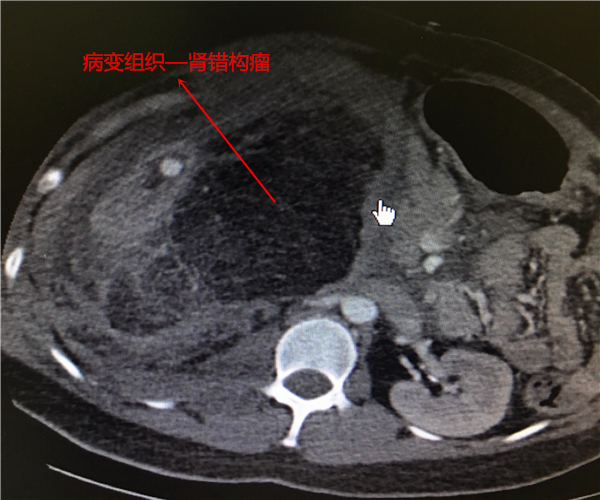

经增强CT检查后,终于发现了端倪——肾错构瘤破裂导致肾出血。